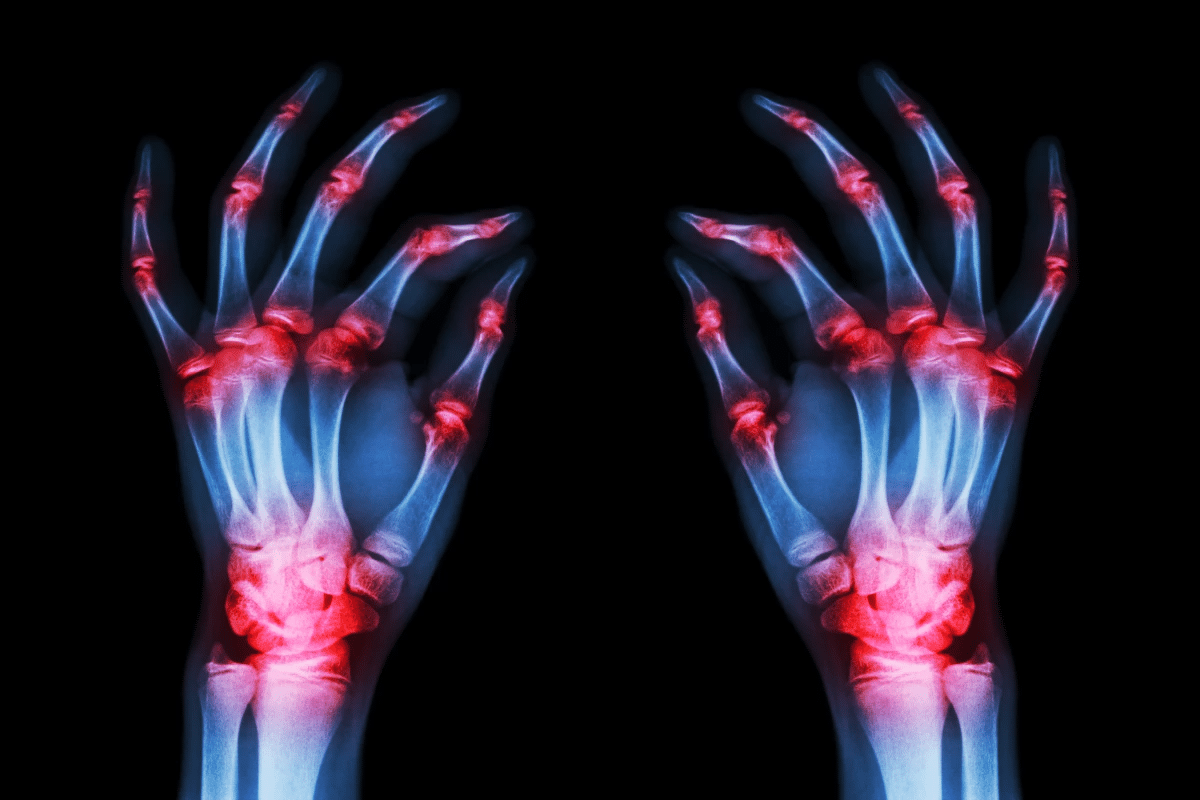

The most common forms of arthritis include osteoarthritis, rheumatoid arthritis, and psoriatic arthritis. Osteoarthritis is characterized by the breakdown of cartilage in joints, leading to pain and stiffness. Rheumatoid arthritis, on the other hand, is an autoimmune condition that causes inflammation and can lead to severe joint damage if not treated promptly. Psoriatic arthritis is associated with the skin condition psoriasis and can cause significant discomfort and disability.

When considering if does arthritis show in an X-ray or does arthritis show on X-ray, it’s essential to understand that X-rays can reveal signs such as joint space narrowing, bone spurs, and erosions. These signs are indicative of various forms of arthritis. The visibility of these signs can depend on the type of arthritis and its stage.

Arthritis shows up differently on X-rays in various joints. It’s key to know these differences for a correct diagnosis. Each joint affected by arthritis has its own X-ray signs, showing how severe it is.

X-rays are great for spotting damage and changes in the hand and wrist with arthritis. You might see:

Arthritis shows up on X-rays as joint space narrowing, bone spurs, and bone cysts. These are signs of joint degeneration and inflammation.